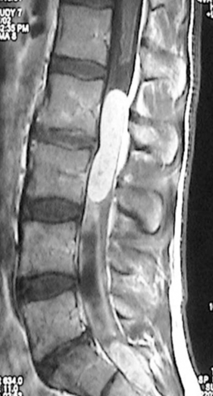

Spinal (vertebral) tumors are either Primary (arising from the vertebra itself) or Secondary/Metastatic (arising from a location other than the spinal column) and can cause either neurological symptoms and/or spinal instability that results in pain and can also cause paralysis from spinal cord compression from tumor or collapse of the spinal column.

They may require multiple modes or combinations of treatment that include surgery, radiation and chemotherapy. Surgical treatment may be limited with laminectomy or major reconstruction depending on the specific situation. Dr Johnson has extensive experience treating these highly variable disorders and had developed many currently used technologies and procedures currently used.